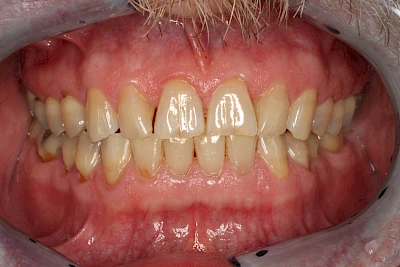

Über die Zeit können verschiedene Prozesse die Zahnhartsubstanzen aufzehren:

- Abnutzung durch Kauen (Abrasion) oder duch durch übermäßiges Knirschen bzw. Pressen (Attrition)

- Säurebedingte Auswaschung (Erosion)

- Knirschen bzw. Pressen und ungünstige Putztechnik (Druck): keilförmige Defekte

Die Zähne können dabei auf Reize (warm, kalt, süß, sauer) oder auch beim Zähneputzen empfindlich oder schmerzhaft sein. In allen diesen Fällen ist es sinnvoll, den Zahnarzt zu kontaktieren und das weitere Vorgehen abzustimmen.